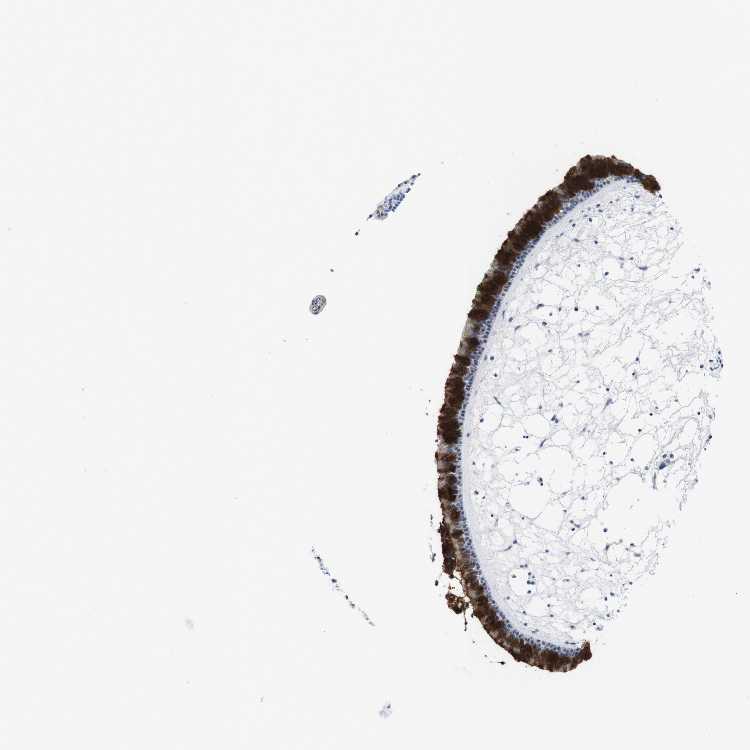

TISSUE PRIMARY DATA NASOPHARYNX Show tissue menu

NASOPHARYNX - Antibody stainingi

Antibody staining in the annotated cell types in the current human tissue is reported as not detected, low, medium, or high, based on conventional immunohistochemistry profiling in selected tissues. This score is based on the combination of the staining intensity and fraction of stained cells.

Each image is clickable and will lead to virtual microscopy that enables deeper exploration of all samples and also displays staining intensity scores, fraction scores and subcellular localization as well as patient and tissue information for each sample.

Antibody HPA011338Antibody CAB026172

Respiratory epithelial cells HighMedium